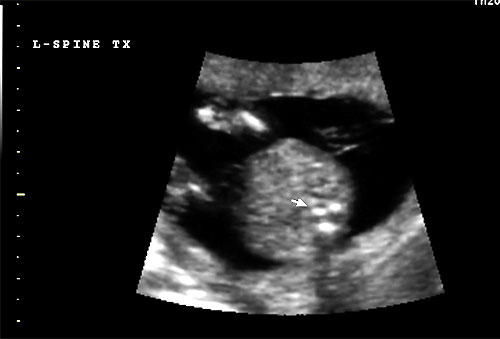

Normal 16 week transverse view of L/S spine |